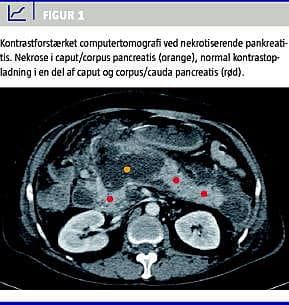

Morfologisk klassifikation

Den morfologiske beskrivelse af sygdommen AP baseres primært på fund gjort ved kontrastforstærket (contrast enhanced ) computertomografi (CECT) [16] (Figur 1 ). Herved kan der defineres tre specifikke sygdomstyper: 1) interstitiel, ødematøs pankreatitis (IEP), 2) nekrotiserende pankreatitis (NP) med nekrose af pankreasparenkymet (samt ofte tillige de peripankreatiske væv) og 3) NP med nekrose af udelukkende de peripankreatiske væv. Atlantaklassifikationen beskrev kun de første to sygdomstyper, hvorimod den isolerede peripankreatiske fedtnekrose, som ses hos op til 20% af patienter med svær AP, ikke blev omtalt som en selvstændig sygdomsenhed. Prognosen for sidstnævnte er generelt bedre end for patienter med intrapankreatiske nekroser [17], men udbredte peripankreatiske nekroser kan, specielt ved komplicerende infektion, også være livstruende.